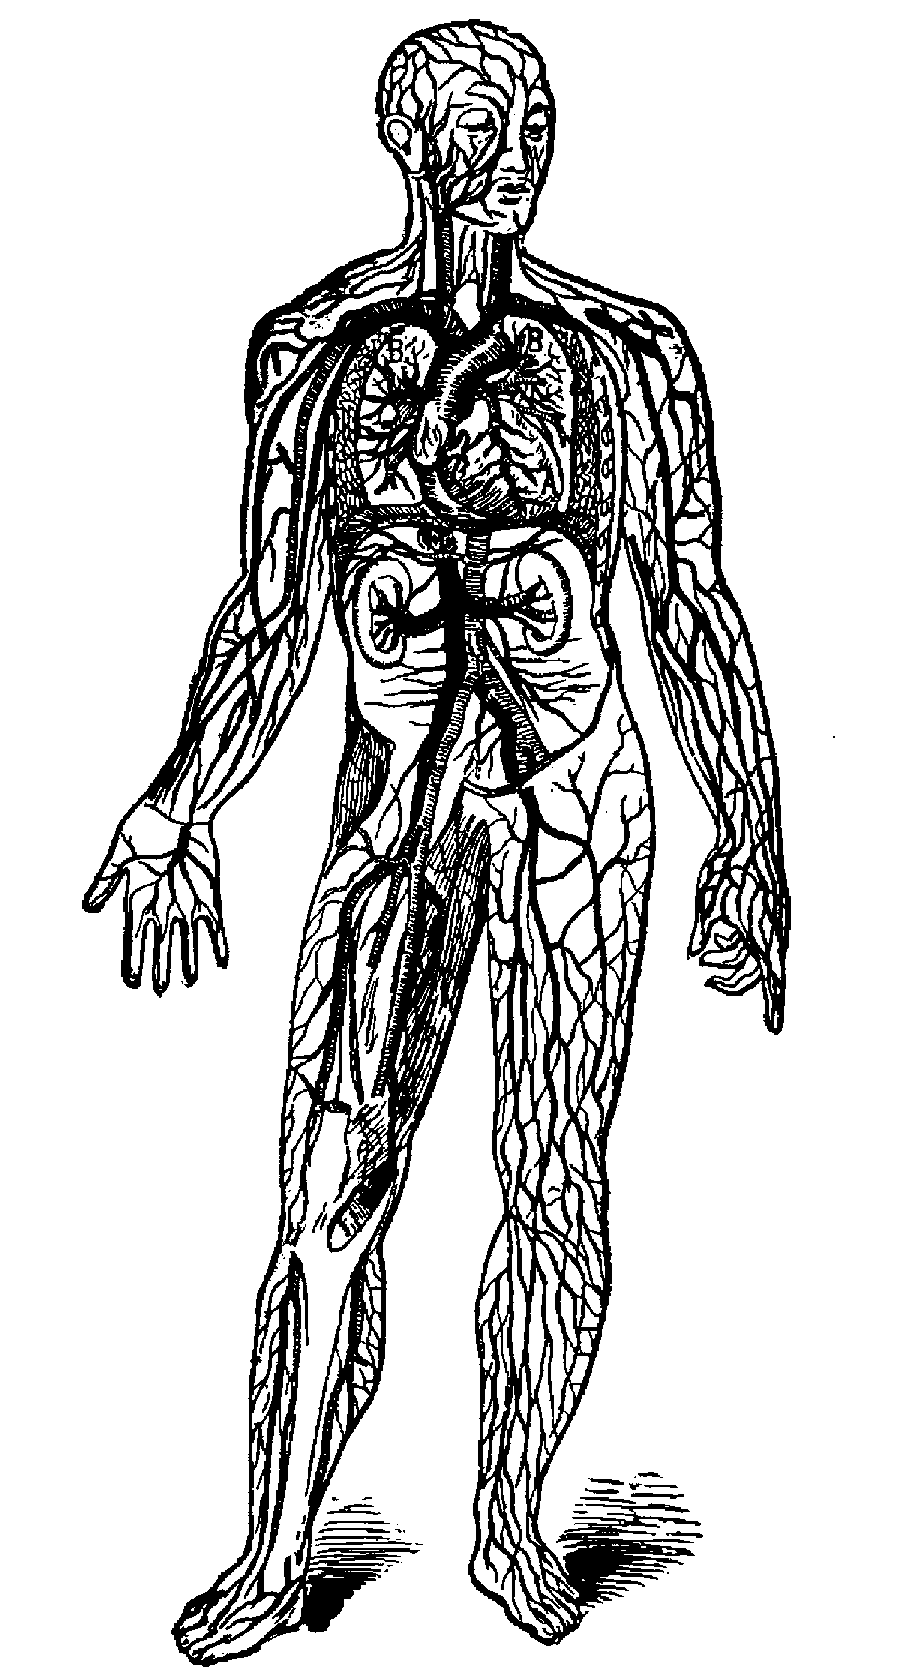

A, the heart; B, the lungs; light cross lines, arteries; heavy lines, veins.

QUESTIONS ON THE INTRODUCTORY LESSONS.

Of what is the body built?—"Of bones."

What covers the bones?—"Flesh."

What covers the flesh?—"Skin."

What flows through the body?—"Blood."

Where does the blood flow from?—"The heart."

When does the blood flow from the heart?—"Every time the heart beats."

Show with your hand how the heart beats.

When does the heart beat?—"All the time."

What happens when the heart stops beating?—"We die."

What do you see on the back of your hand, beneath the skin?—"Veins"

What is in the veins?—"Bad blood."

What are the veins?—"Pipes for the bad blood to pass through."

Where do the veins carry the bad blood?—"To the heart."

Where does the heart send the bad blood?—"To the lungs."

What happens to the bad blood when in the lungs?—"It is made pure."

What makes the bad blood pure?—"The air."

How does the air get into the lungs?—"Through my nose, mouth, and windpipe."

What is breathing?—"Letting the air into and out of my lungs, through my nose, mouth, and windpipe."

When do you breathe?—"All the time."

What do you breathe?—"Air."

What do you breaths through?—"My nose, mouth, and windpipe."

Where do you get the air?—"Everywhere."

Where do the lungs send the pure blood?—"To the heart."

Where does the heart send the pure blood?—"All through the body."

How does the heart send the pure blood through the body?—"Through pipes called arteries."

What kind of blood passes through the arteries?—"Pure blood."

What kind of blood passes through the veins?—"Impure blood."

What carries the pure blood through the body?—"The arteries."

What carries the impure blood through the body?—"The veins."

FORMULA FOR THE LESSON ON THE HEART AND THE CIRCULATION OF THE BLOOD.

1. My heart is shaped like a cone, and placed in my chest near my breastbone, with its apex pointing downward to my left side. It beats about seventy times a minute, sending out about two ounces of blood at every beat.

2. The blood when pure is of a bright red color; it is a liquid made from food and drink.

3. It passes from my heart to all parts of my body, through pipes called arteries; these arteries spread out through the body like branches from a tree.

4. As the blood flows from the heart, through the arteries, it gives nourishment to every part of the body, and carries away the impurities it meets, which makes it black and thick; when it comes through the veins, back to the heart, it is not fit to be used, so it goes to the lungs to be purified by the fresh air; then it returns to the heart to be sent again throughout the body; this happens once in from three to eight minutes, and is called the circulation of the blood.